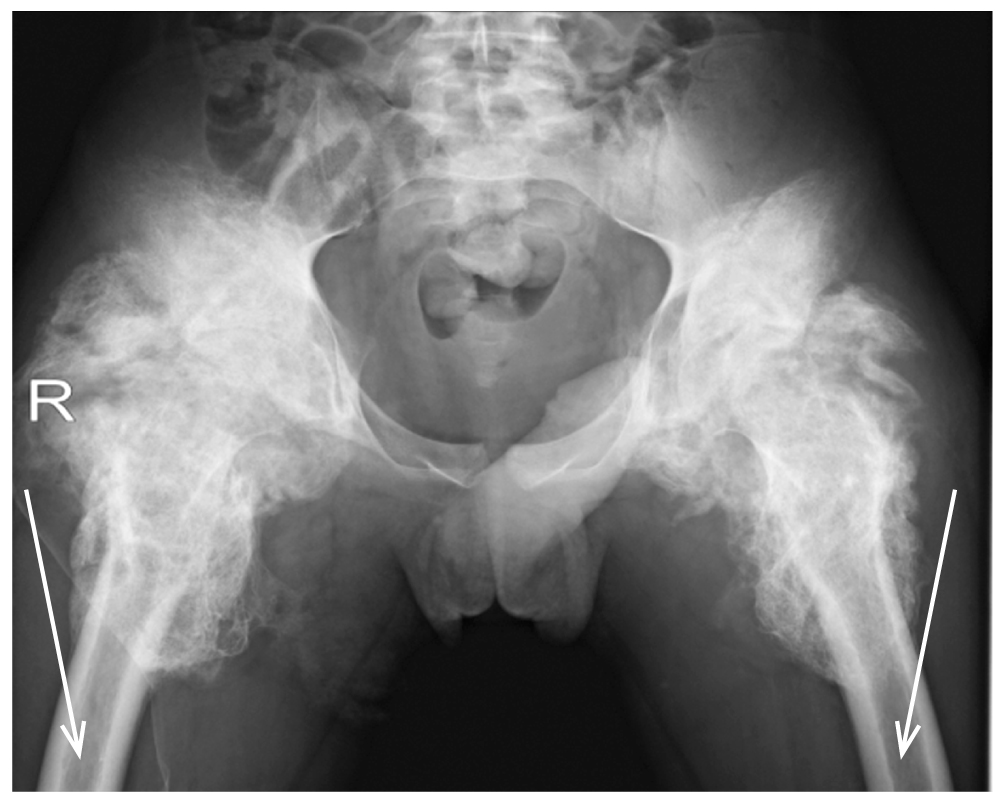

На реабилитацию с тромбозами нижних конечностей в стадии реканализации поступили 12 (19,7%) детей этой группы, у 5 (8,2%) из них была выявлена мочекаменная болезнь (рис. 2). У 3 (14,3%) детей II группы при поступлении на реабилитацию были выявлены гетеротопические оссификации (рис. 3).

Рис. 3. Рентгенологическая картина пациента с позвоночно-спинномозговой травмой на уровне С5–С6 (3 мес после травмы): массивные гетеротопические оссификаты в области тазобедренных суставов в проекции от крыльев подвздошных костей до верхней трети диафизов бедренных костей, регионарный остеопороз (стрелка). / Fig. 3. X-ray picture of massive heterotopic ossifications in the area of the hip joints in the projection from the wings of the iliac bones, up to 3 of the diaphysis of the femur, regional osteoporosis (arrow) in a patient with at the level of C5–C6 (3 months after injury).